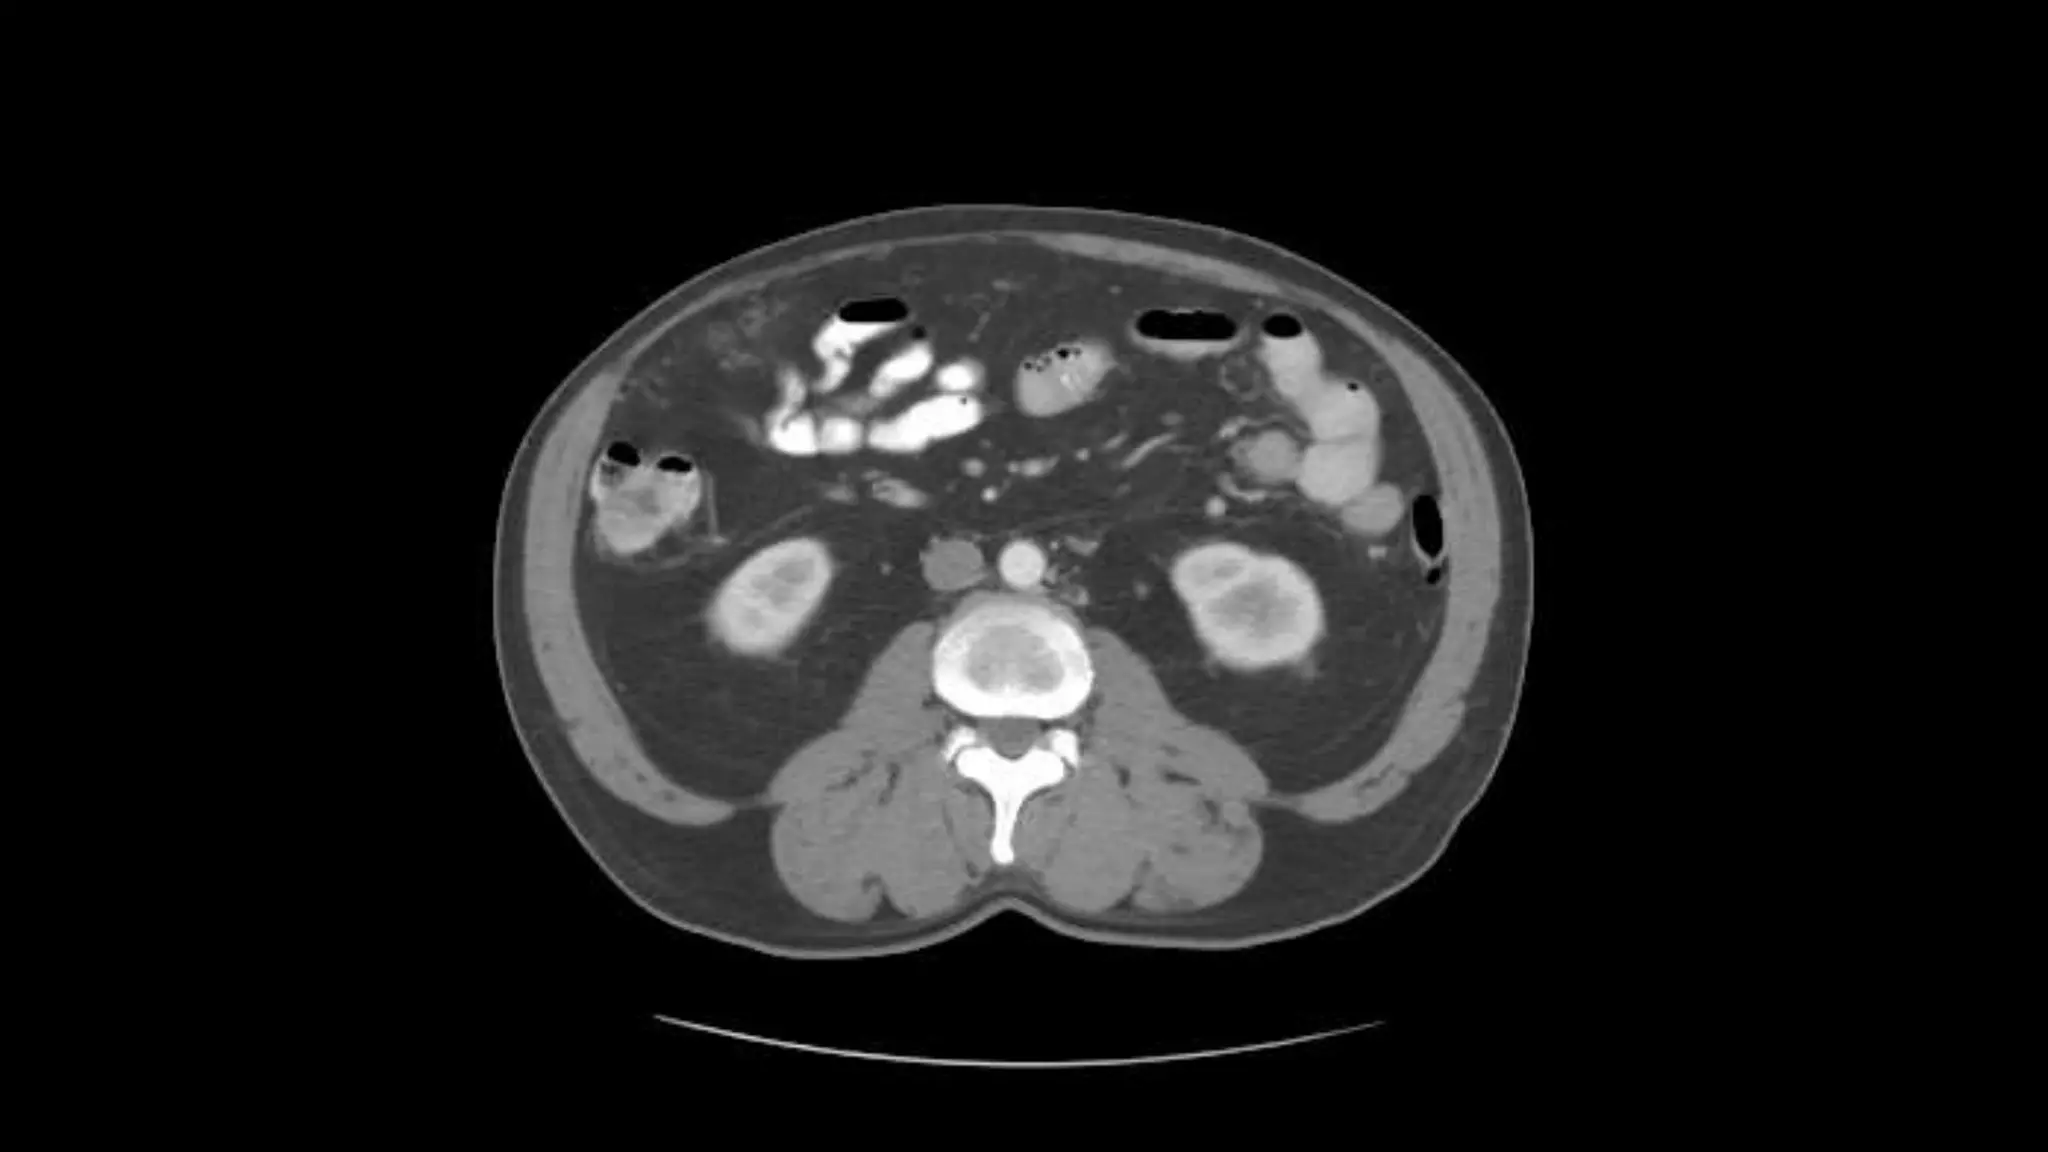

Rt. and Lt.Kidneys

Renal Veins emptying into the IVC. We also see the right renal artery branching

off the Aorta, follow it down till you see it enter the right kidney. The Superior

Mesenteric Vein is outlined on the top of this image. If you follow the SMV up, you

will see it empty into the Portal Vein.

Here we see the right and left renal vein entering into the Inferior Vena Cava. We

Also see the left renal artery branching off the aorta and heading toward the left

kidney. Page up and down to trace these vessels.